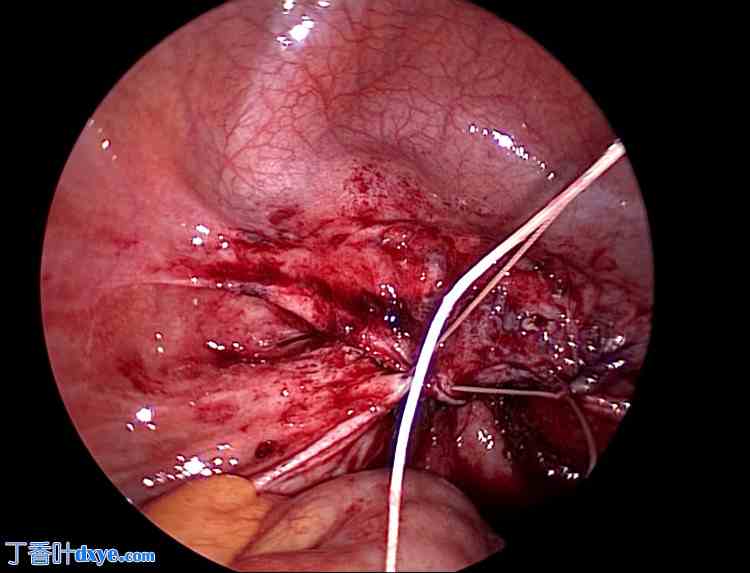

对阴道残端的脆弱组织进行清创。清创后,用生理盐水充分冲洗周围区域。随后,在腹腔镜引导下经阴道缝合伤口(图 7-9)。首先,在腹腔镜的引导下,经阴道缝合阴道壁。然后,从腹腔侧缝合腹膜,形成双层缝合。

图 7. 阴道壁缝合后。